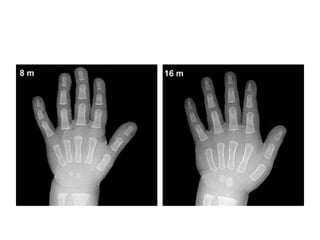

Toddlers

• Females: 10 months to 2 years of age

• Males: 14 months to 3 years of age

• The ossification centers for the epiphyses of all

phalanges and metacarpals become

recognizable during this stage, usually in the

middle finger first, and the fifth finger last.

• Bone age determinations are primarily based on the assessment

of the number of identifiable epiphyseal ossification centers,

which generally appear in an orderly characteristic pattern, as

follows

• 1) Epiphyses of the proximal phalanges;

• 2) Epiphyses of the metacarpals;

• 3) Epiphyses of the middle phalanges; and,

• 4) Epiphyses of the distal phalanges.

• The number and degree of maturation of the carpal bones in

the wrist are

• less useful indicators at this stage, as only three or four

(capitate, hamate and lunate and, at times, trapezoid) are

recognizable.

• Two common exceptions to this rule are:

1) The early appearance of the ossification

center of the distal phalanx of the thumb,

which is usually recognizable at 1 year and 3

months in males, and 1 year and six months

in females;

• The late appearance of the ossification center

of the middle phalanx of the fifth finger, which

is the last phalangeal epiphysis to appear.